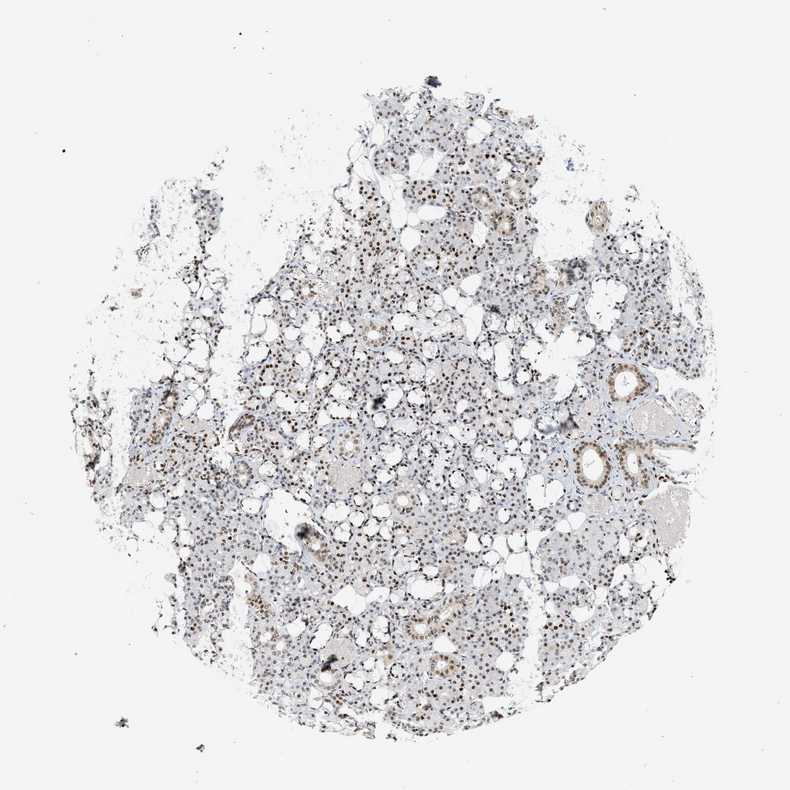

SALIVARY GLAND - Antibody stainingi

Antibody staining in the annotated cell types in the current human tissue is reported as not detected, low, medium, or high, based on conventional immunohistochemistry profiling in selected tissues. This score is based on the combination of the staining intensity and fraction of stained cells.

Each image is clickable and will lead to virtual microscopy that enables deeper exploration of all samples and also displays staining intensity scores, fraction scores and subcellular localization as well as patient and tissue information for each sample.

Antibody HPA022961Antibody HPA024457

Glandular cells HighHigh